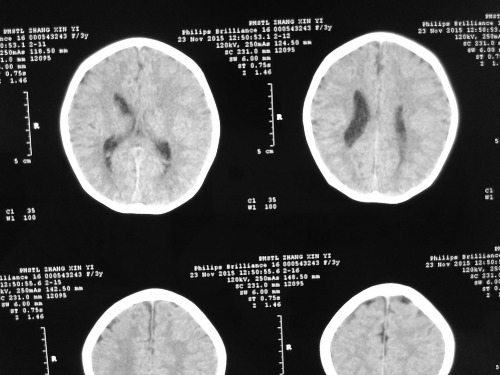

PED5224:3岁女孩。

3岁女孩,多动症,左侧脑室前角发育不良,MRI显示侧脑室内异常信号,T1高信号,T2低信号,压脂低信号。

考虑左侧侧脑室粘合可能。